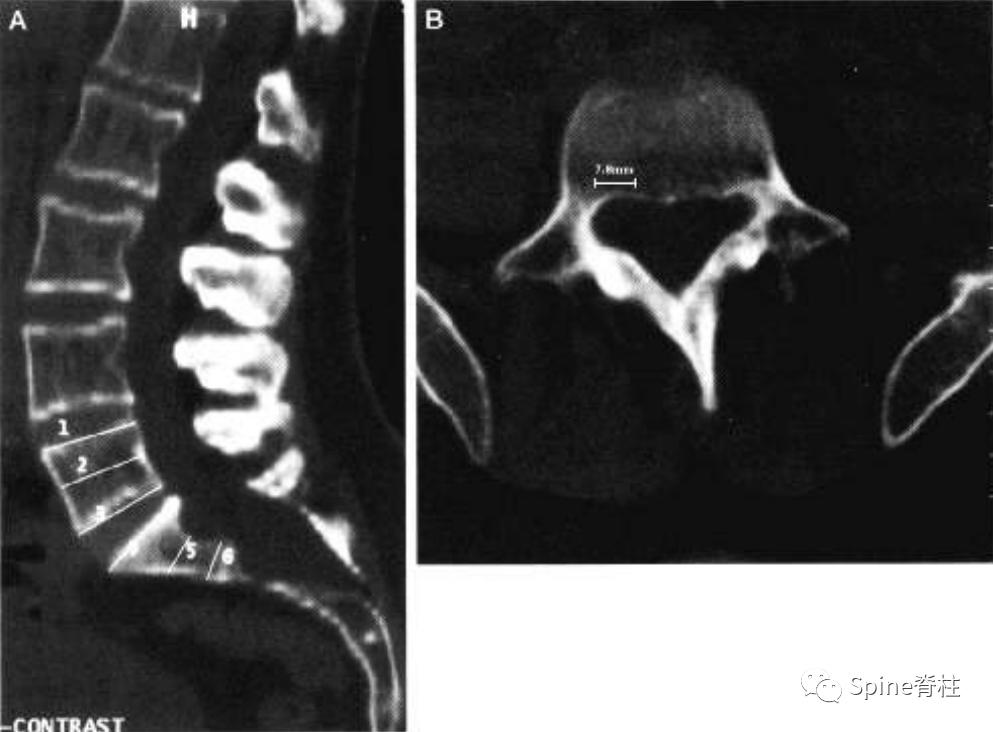

一位马凡综合征伴硬膜扩张患者的CT图像。a为正中矢状位重建,可见S2的椎管宽度大于L4。S1扇形缺损值为4.2mm。b为L5水平的横断面提示一个神经根袖的直接为6.6mm。因此,这个患者满足一个主要标准和两个次要标准。